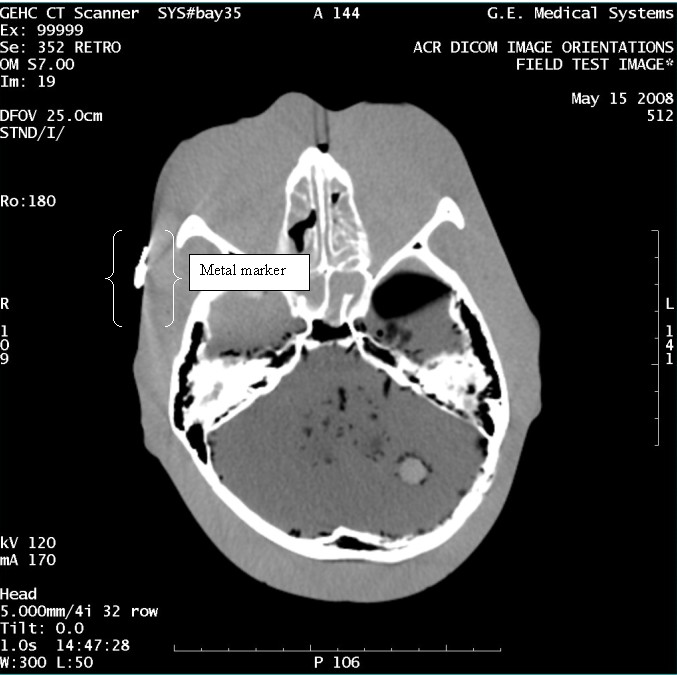

- With the support of the site personnel, examine the images sent

to the Review Station (i.e., 12 series, each with 1 image) and compare

their orientation to the images in this document.

- Each image contains a metal marker on the phantom's right cheek.

- Each image in this document contains a description of the expected

orientation of the metal marker (i.e. to prove Left and Right) as

well as the Posterior and Anterior orientation description.note:

The sample images included in this document use “R”, “L”, “P”, and “A” for “Right”, “Left”, “Posterior” and “Anterior” orientation. The Hospital Review Station may use a different style of annotation. The style used is not relevant to this procedure.

Figure 11. Exam 99999, Series 352